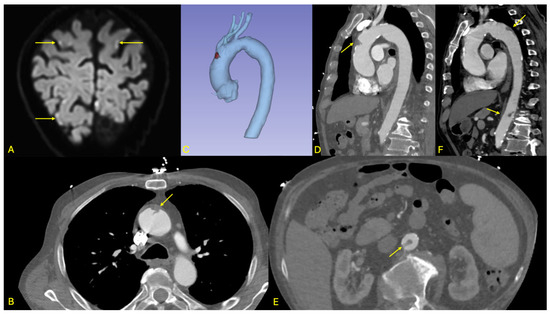

Figure 3. Overview of initial and follow-up imaging findings in patient 2. (A): Diffusion-weighted MRI sequence displayed in oblique coronal view showing multiple dot-like cortical hyperintensities of the posterior and pre-central regions (arrows), consistent with embolic stroke. (BD): Axial and sagittal views as well as 3D multiplanar reconstruction from the initial ECG-gated CT angiography of the aorta, showing an endoluminal thrombus attached to a soft-plaque (arrow) of the anterior aspect of the ascending aorta and bulging into the aortic lumen. (E): Axial view from the initial aortic CT angiography showing a second, more tubular thrombus of the subrenal aorta (arrow). (F): Follow-up CTA showing regression of the thrombus in the ascending aorta, as well as two new thrombi (arrows), in front of the isthmus and at the thoraco-abdominal junction; the subrenal thrombus had resolved.

Brain magnetic resonance imaging (MRI) demonstrated multiple acute ischemic lesions involving both supratentorial and infratentorial regions, with some foci exhibiting hemorrhagic transformation. The distribution of lesions across multiple vascular territories was suggestive of an embolic etiology, although the exact timing of the ischemic events remained unclear (see Figure 3).

Initial non-contrast CT imaging incidentally revealed a floating thrombus within the aortic arch, prompting further evaluation with an urgent contrast-enhanced CT angiography. The angio-CT confirmed the presence of a stable, mobile thrombus located in the distal ascending aorta (see Figure 3). Additionally, the scan identified a small ulcerated atherosclerotic plaque in the abdominal aorta just proximal to the origin of the celiac trunk, as well as a second floating thrombus in the subrenal segment of the abdominal aorta. No evidence of ischemia was detected in the solid intra-abdominal organs, and the splanchnic arterial branches remained patent.